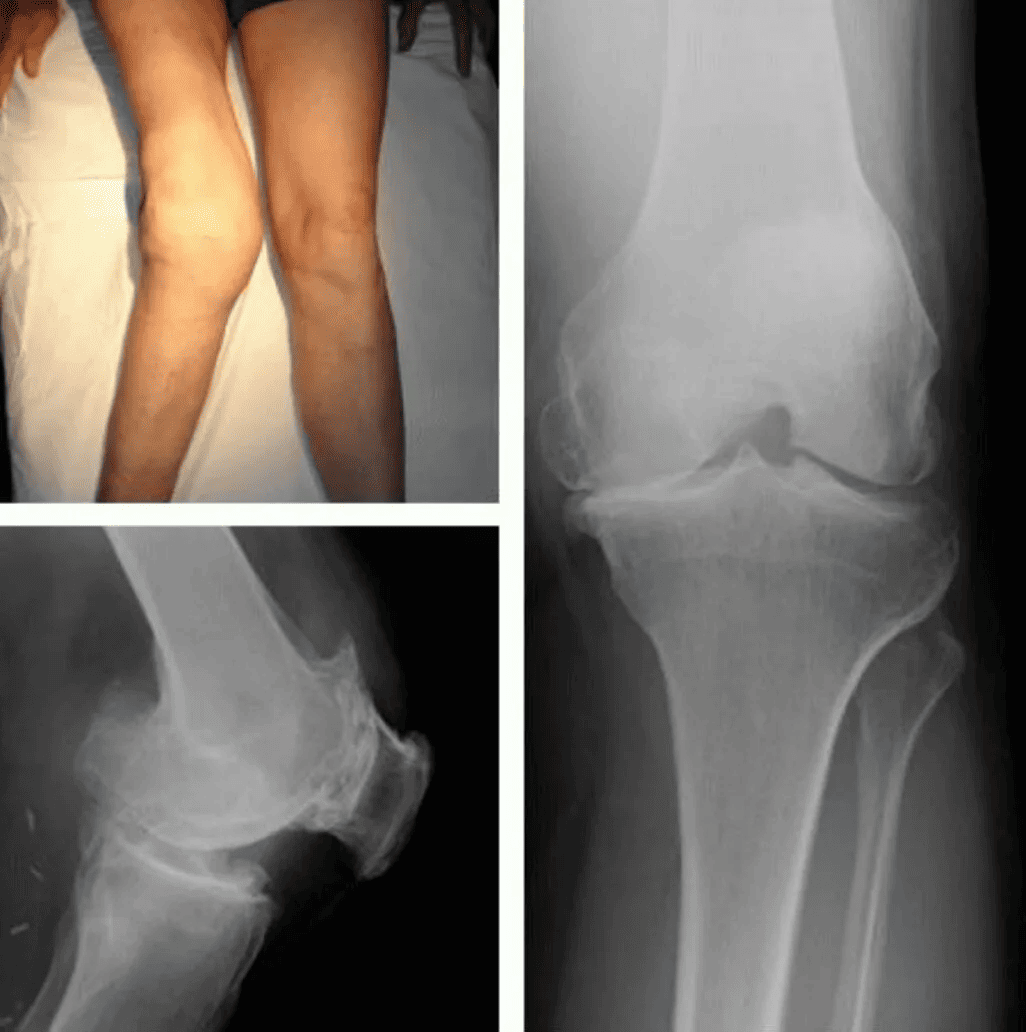

Namun pada usia 28 tahun, saya didiagnosis menderita osteoartritis. Kata ini tidak berarti apa-apa bagi saya pada saat itu, tetapi segera menjadi kutukan bagi saya. Pada awalnya itu hanya ketidaknyamanan. Sedikit rasa sakit di lutut yang saya abaikan. Saya berkata pada diri saya sendiri: “Ini hanya sementara, hanya kelelahan”. Namun hari demi hari, rasa sakitnya semakin parah. Saya tidak bisa lagi berdiri di satu tempat untuk waktu yang lama, saya tidak bisa berjalan bahkan selama satu jam.